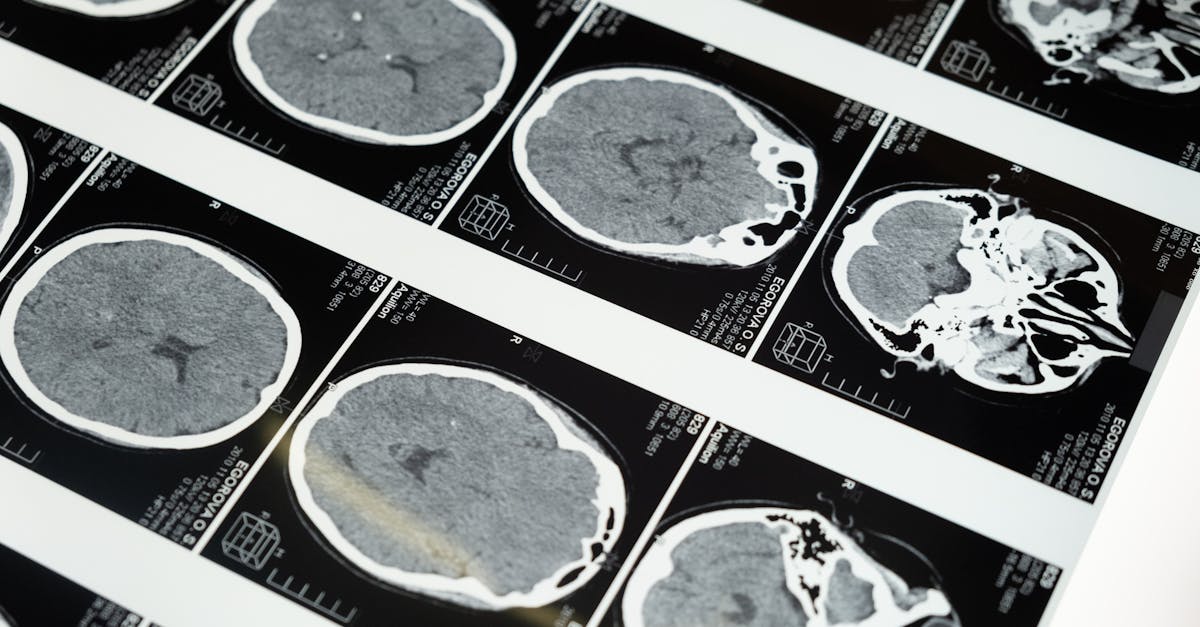

9. Brain Tumors and Space-Occupying Lesions - Silent Growth with Varied Presentations

Brain tumors can present with an incredibly diverse array of symptoms depending on their location, size, and rate of growth, often mimicking other neurological conditions. Slowly growing tumors, such as meningiomas, may present with gradual cognitive changes that can be mistaken for dementia or depression. Frontal lobe tumors can cause personality changes and executive dysfunction that may be attributed to psychiatric conditions. Temporal lobe tumors can present with seizures, memory problems, or language difficulties that may be confused with epilepsy or other neurological conditions. Pituitary tumors can cause visual field defects that may be mistaken for optic nerve disorders or stroke. Brain metastases can present with sudden onset neurological symptoms that closely mimic stroke, particularly when they are associated with hemorrhage. Primary central nervous system lymphoma can present with cognitive changes and focal neurological deficits that may be mistaken for other conditions, particularly in immunocompromised patients. The challenge in diagnosing brain tumors is that many of the presenting symptoms are common and nonspecific, such as headaches, which are experienced by a large percentage of the population. Additionally, some brain tumors can remain asymptomatic for long periods, only becoming apparent when they reach a critical size or location. The development of advanced neuroimaging techniques has improved the ability to detect and characterize brain tumors, but the clinical presentation often remains the key to suspecting their presence.